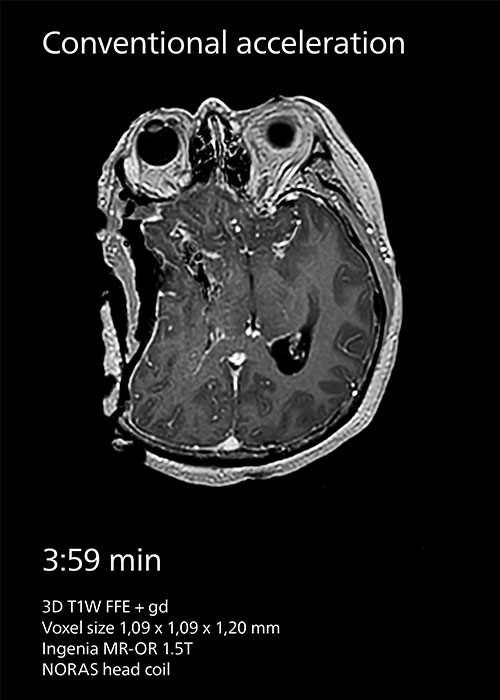

Because imaging speed in intraoperative MRI is important at Tokai, the center has been using SENSE parallel imaging since the beginning. In 2020, the team started employing Compressed SENSE instead to achieve greater scan time reductions. “At our hospital we prioritize speed and we have seen that Compressed SENSE helps us to reduce intraoperative MRI scan

time for our 3D T1W scans with about 40%.” Dr. Matsumae says.

Compressed SENSE reduces scan time from 3:59 min to 2:55 min with the same spatial resolution.